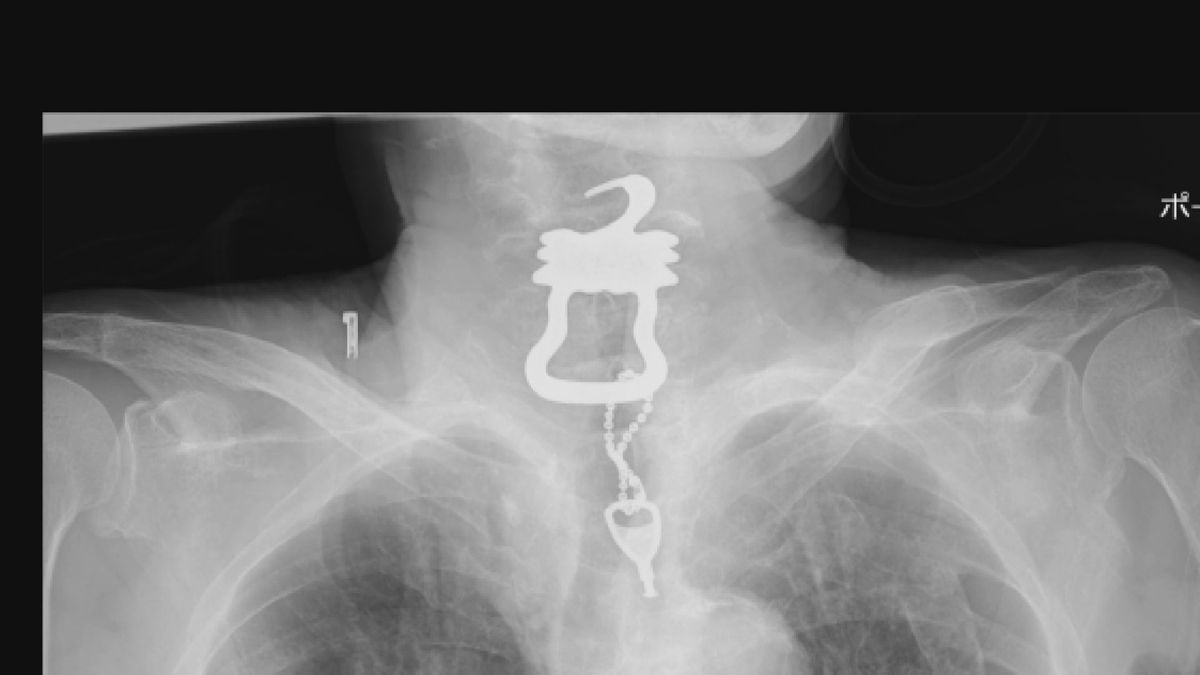

しかし、その年の9月、喉の痛みを訴えたあと新型コロナウイルスと診断されます。病院が胸のレントゲンを撮ったところ、喉にカギが見つかり摘出されましたが、数日後に死亡しました。■喉に「カギ」なぜ?

「カギ」は約12センチ。金属製のキーホルダーがついていました。遺族によると軽度の認知症と診断されていた健一さんは入院中、点滴などに触らないようにファスナー付きの“つなぎ服”を着用していました。

“つなぎ服”のファスナーはカギをかけるタイプのもので、病院側はカギをベッド近くのテーブルに置き忘れていた可能性が高いと2023年に回答していたということです。■遺族が病院側を提訴